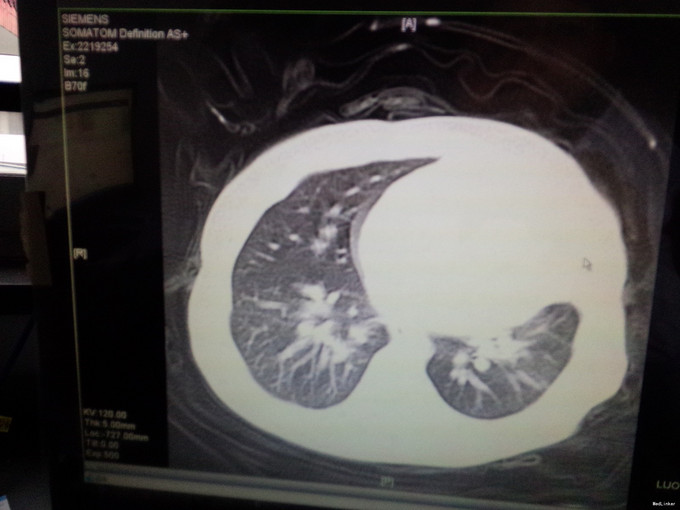

女,4月,咳嗽4-5天,加重一天。4-5天出现咳嗽,不发热,在诊所就诊予以对症处理(具体用药不详),疗效不佳,咳嗽症状加重,气促明显,近2天患儿吃奶差,无呕吐,大便呈稀水样改变。体检:神清,精神差,呼吸急促50次i/分,HR140次/分,两肺可闻及明显的湿罗音,心脏未闻及明显病理性杂音。肺部CT提示肺不张,心脏B超提示室间隔缺损(基底部)。血RT:WBC16.87*109/l,免疫球蛋白水平低.

呼吸急促50次i/分,HR140次/分,两肺可闻及明显的湿罗音,心脏未闻及明显病理性杂音。肺部CT提示肺不张,心脏B超提示室间隔缺损(基底部)。血RT:WBC16.87*109/l,免疫球蛋白水平低.